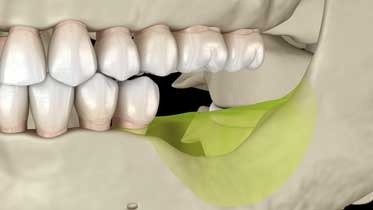

Решение 1. Наращивание костной ткани (костная пластика)

Этот метод выбираем, когда кости недостаточно даже для минимального импланта и когда важно восстановить естественный контур десны — например в зоне улыбки.

Суть процедуры в том, чтобы создать условия для роста костной ткани там, где её не хватает. Врач добавляет в зону дефицита костный материал — синтетический, донорский или ваш собственный, а организм постепенно интегрирует его. Процесс занимает 3-6 месяцев, но результат получается прочным и надёжным.

После этого в нарощенную кость устанавливаем имплант. Да, это требует времени и терпения. Но взамен вы получаете физиологичное восстановление зуба, который прослужит десятилетия.